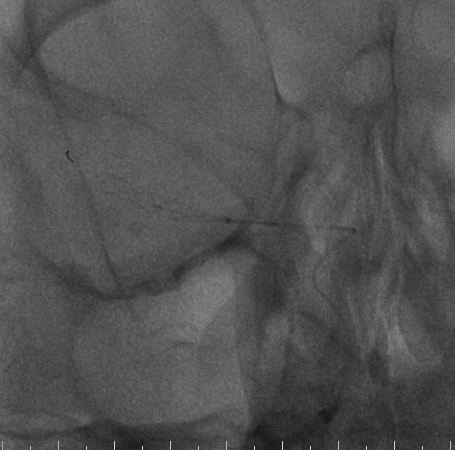

手术过程

右侧桡动脉穿刺置入6F 泰尔茂薄壁鞘,Cat5中间导管同轴rebar27导管头端塑形在0.014微导丝引导下引至右侧颈内动脉海绵窦段,Cat5中间导管引入V18导丝加强系统支撑。

畅医达(Accessway)0.017支架微导管在0.014微导丝引导下顺利到达右侧大脑中动脉M2远端,经支架微导管引入畅医达(Choydar)血流导向装置,3mm*15mm,推送平顺,然后跨瘤颈缓慢释放支架,支架头端打开良好。